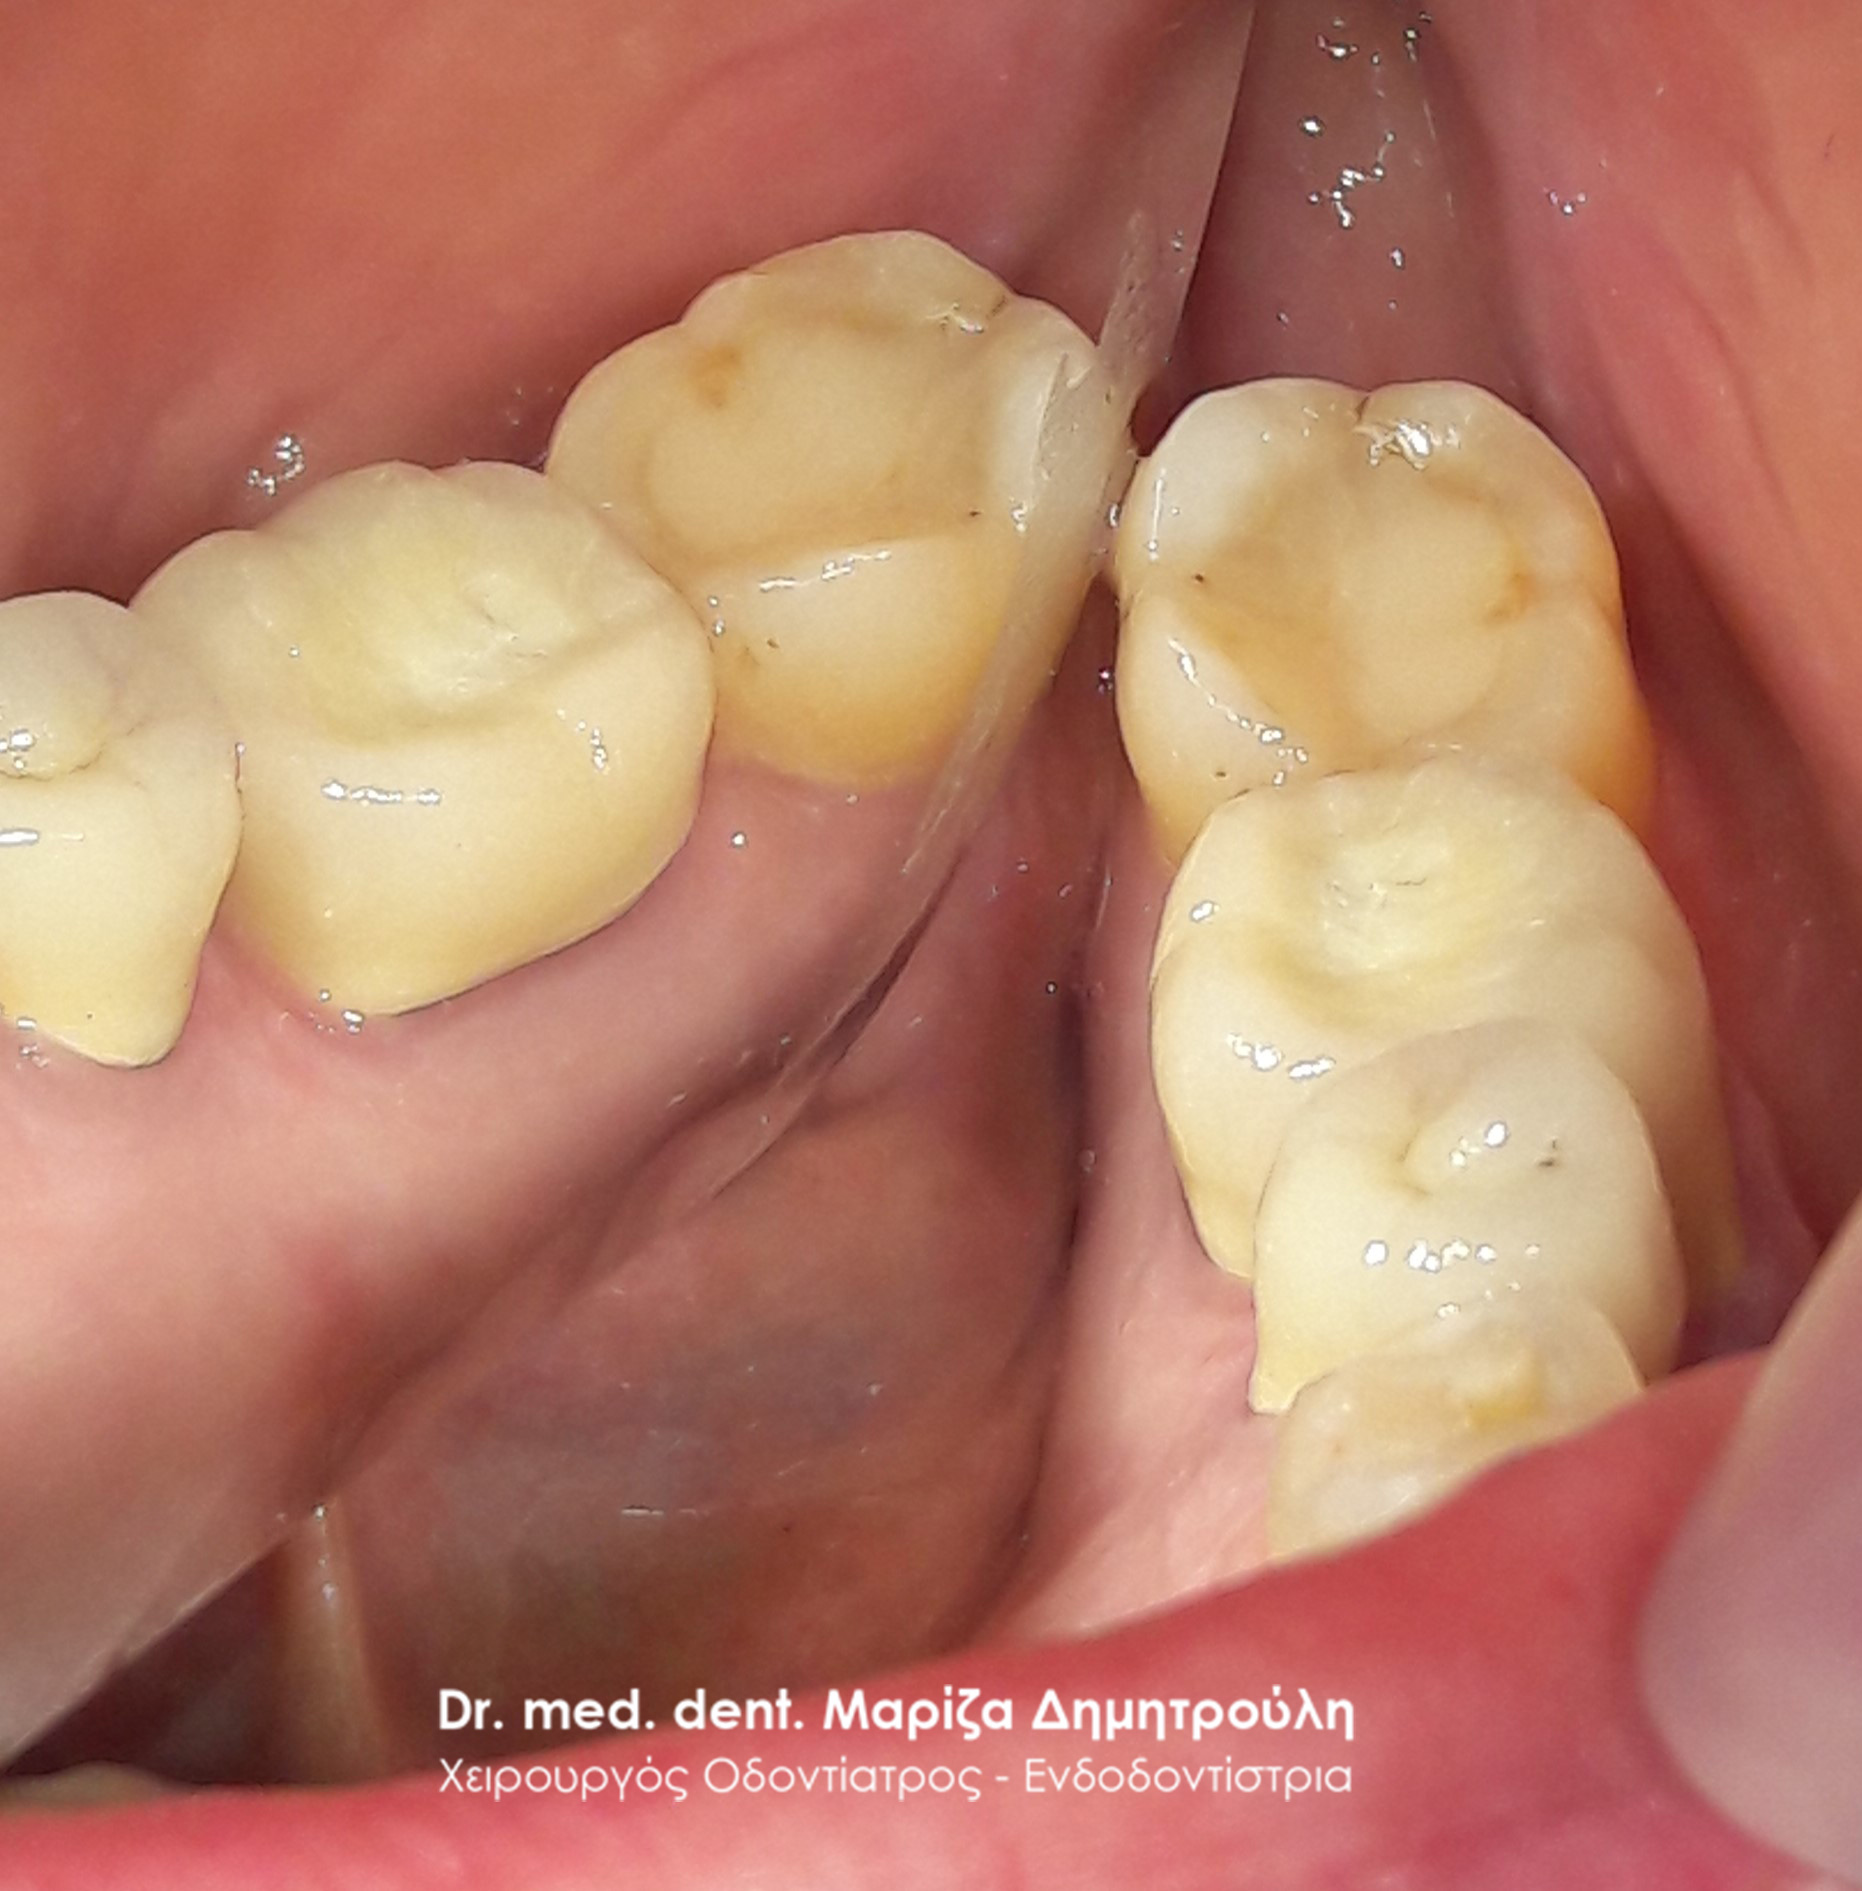

Αρχική κλινική εικόνα του μεγάλου οδοντικού ελλείμματος

Τελική κλινική εικόνα του ολοκεραμικού επένθετου στο γομφίο